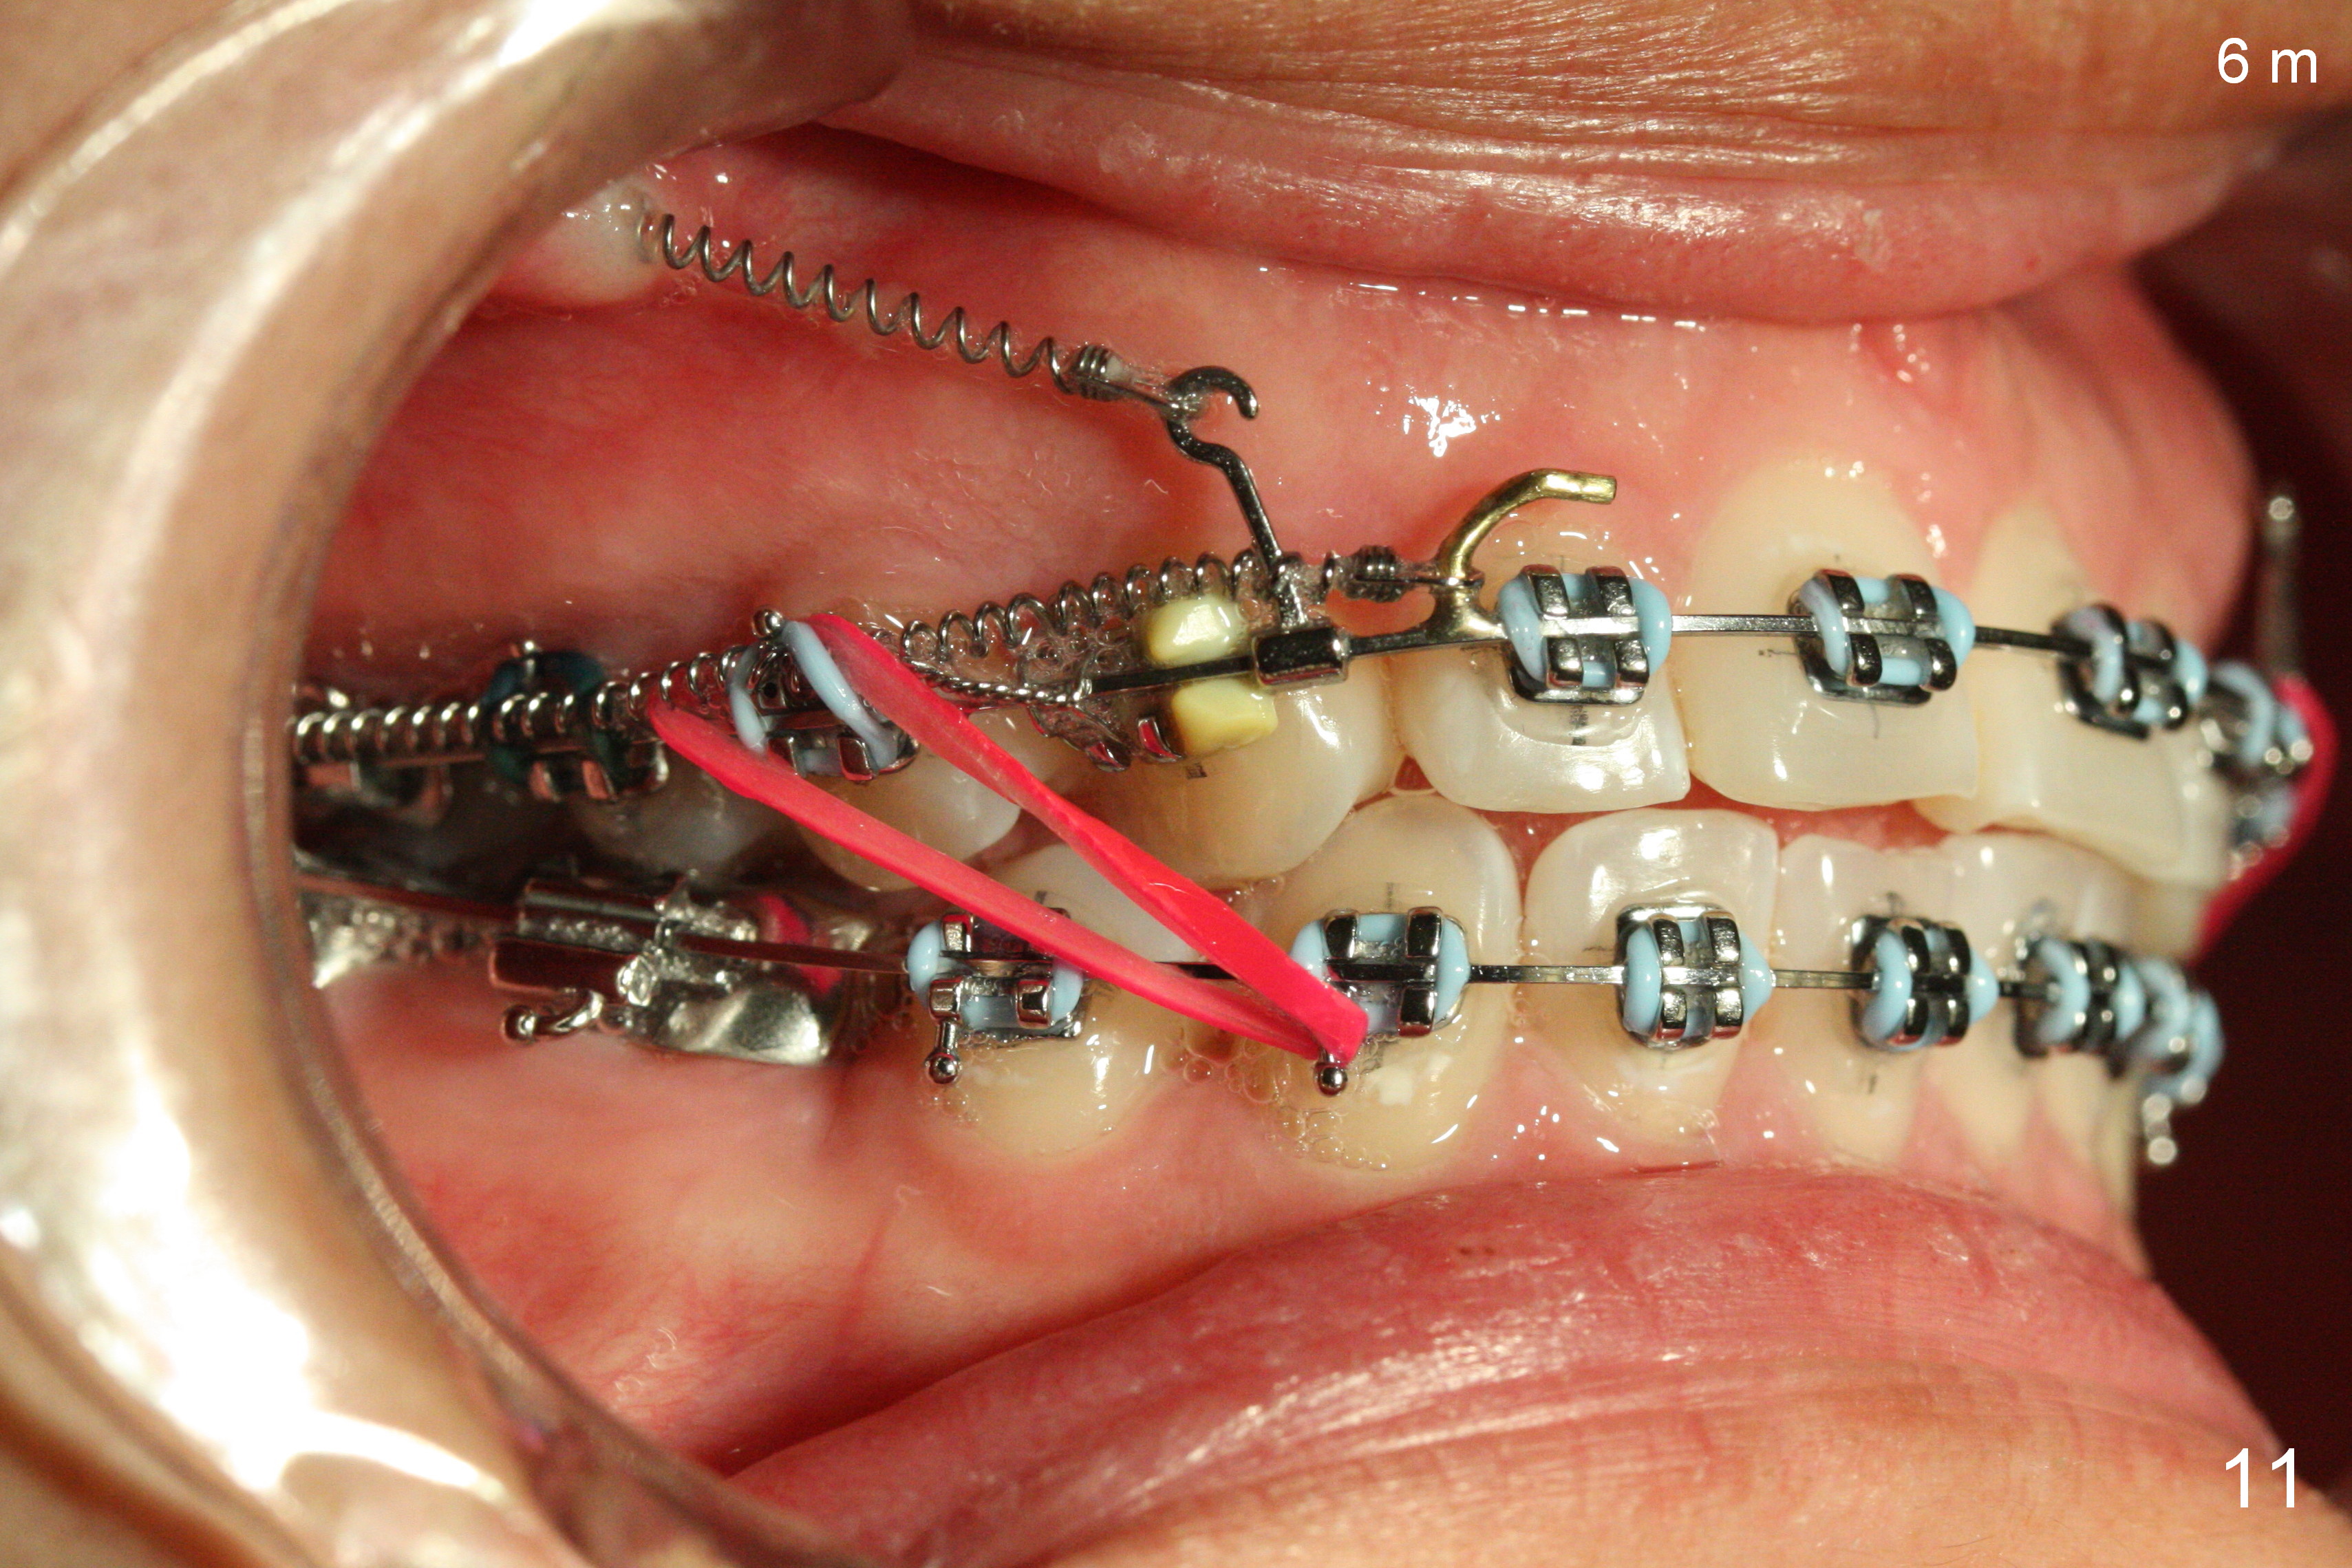

Postop follow up at 1 week (Fig.5,6), 2 months (Fig.7,8) and 3 months (Fig.9,10).  Granulation tissue forms around the entrance of closed coil spring with tenderness 2 months postop (Fig.7,8).  Pain persists especially on the left.  Tension of coiled spring associated with zygomatic implants is low; new coiled springs are added for the posterior implants (Fig.9,10).  Later the left spring associated with the left zygomatic implant fractures.

Six months post zygomatic implants, the profile, anterior overbite and overjet and the right posterior interdigitation are within normal limit (Fig.11), whereas the left one not (Fig.12).  The lower midline appears to be deviated to the left.  Elastics are used for correction (Fig.11,13,14).  A second option is to reduce the number of closed springs on the right and increase the one on the left.